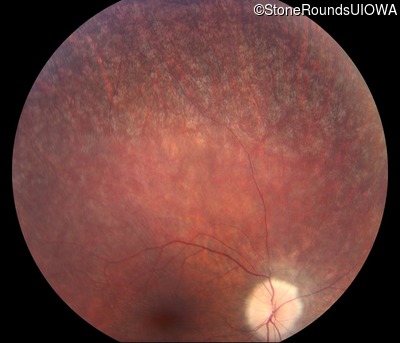

Fundus Photography - Right - 10/100 -1 sc

Exemplar